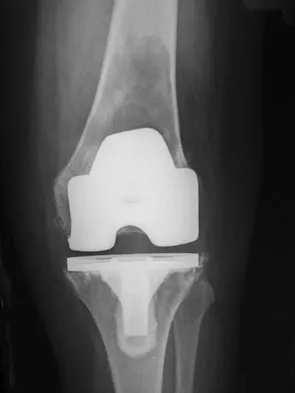

Figure 3 shows the AP radiograph of a patient with diabetes mellitus who has knee pain. A semiconstrained knee prosthesis was used in this patient to prevent which of the following complications?

Explanation

The radiographic appearance of the joint is highly suspicious for neuropathic joint (Charcot's joint). Evidence of bone loss on both the tibial and the femoral sides may necessitate the use of metal and/or bone augments. Patients with a neuropathic joint often have excellent range of motion, and postoperative stiffness is not a problem. The main problem with these patients is instability that occurs secondary to ligamentous laxity. Use of a semiconstrained prosthesis prevents the latter complication. Parvizi J, Marrs J, Morrey BF: Total knee arthroplasty for neuropathic (Charcot) joints. Clin Orthop 2003;416:145-150.